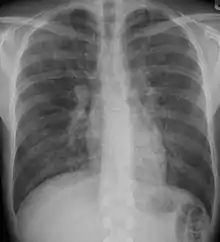

Radiografia de tórax é geralmente o primeiro teste para detectar doenças pulmonares intersticiais, mas a radiografia de tórax pode ser normal em até 10% dos pacientes, especialmente no início do processo da doença. A Tomografia Computadorizada de alta resolução do tórax é o melhor exame de imagem para diagnosticar e classificar doenças pulmonares intersticiais.[3]